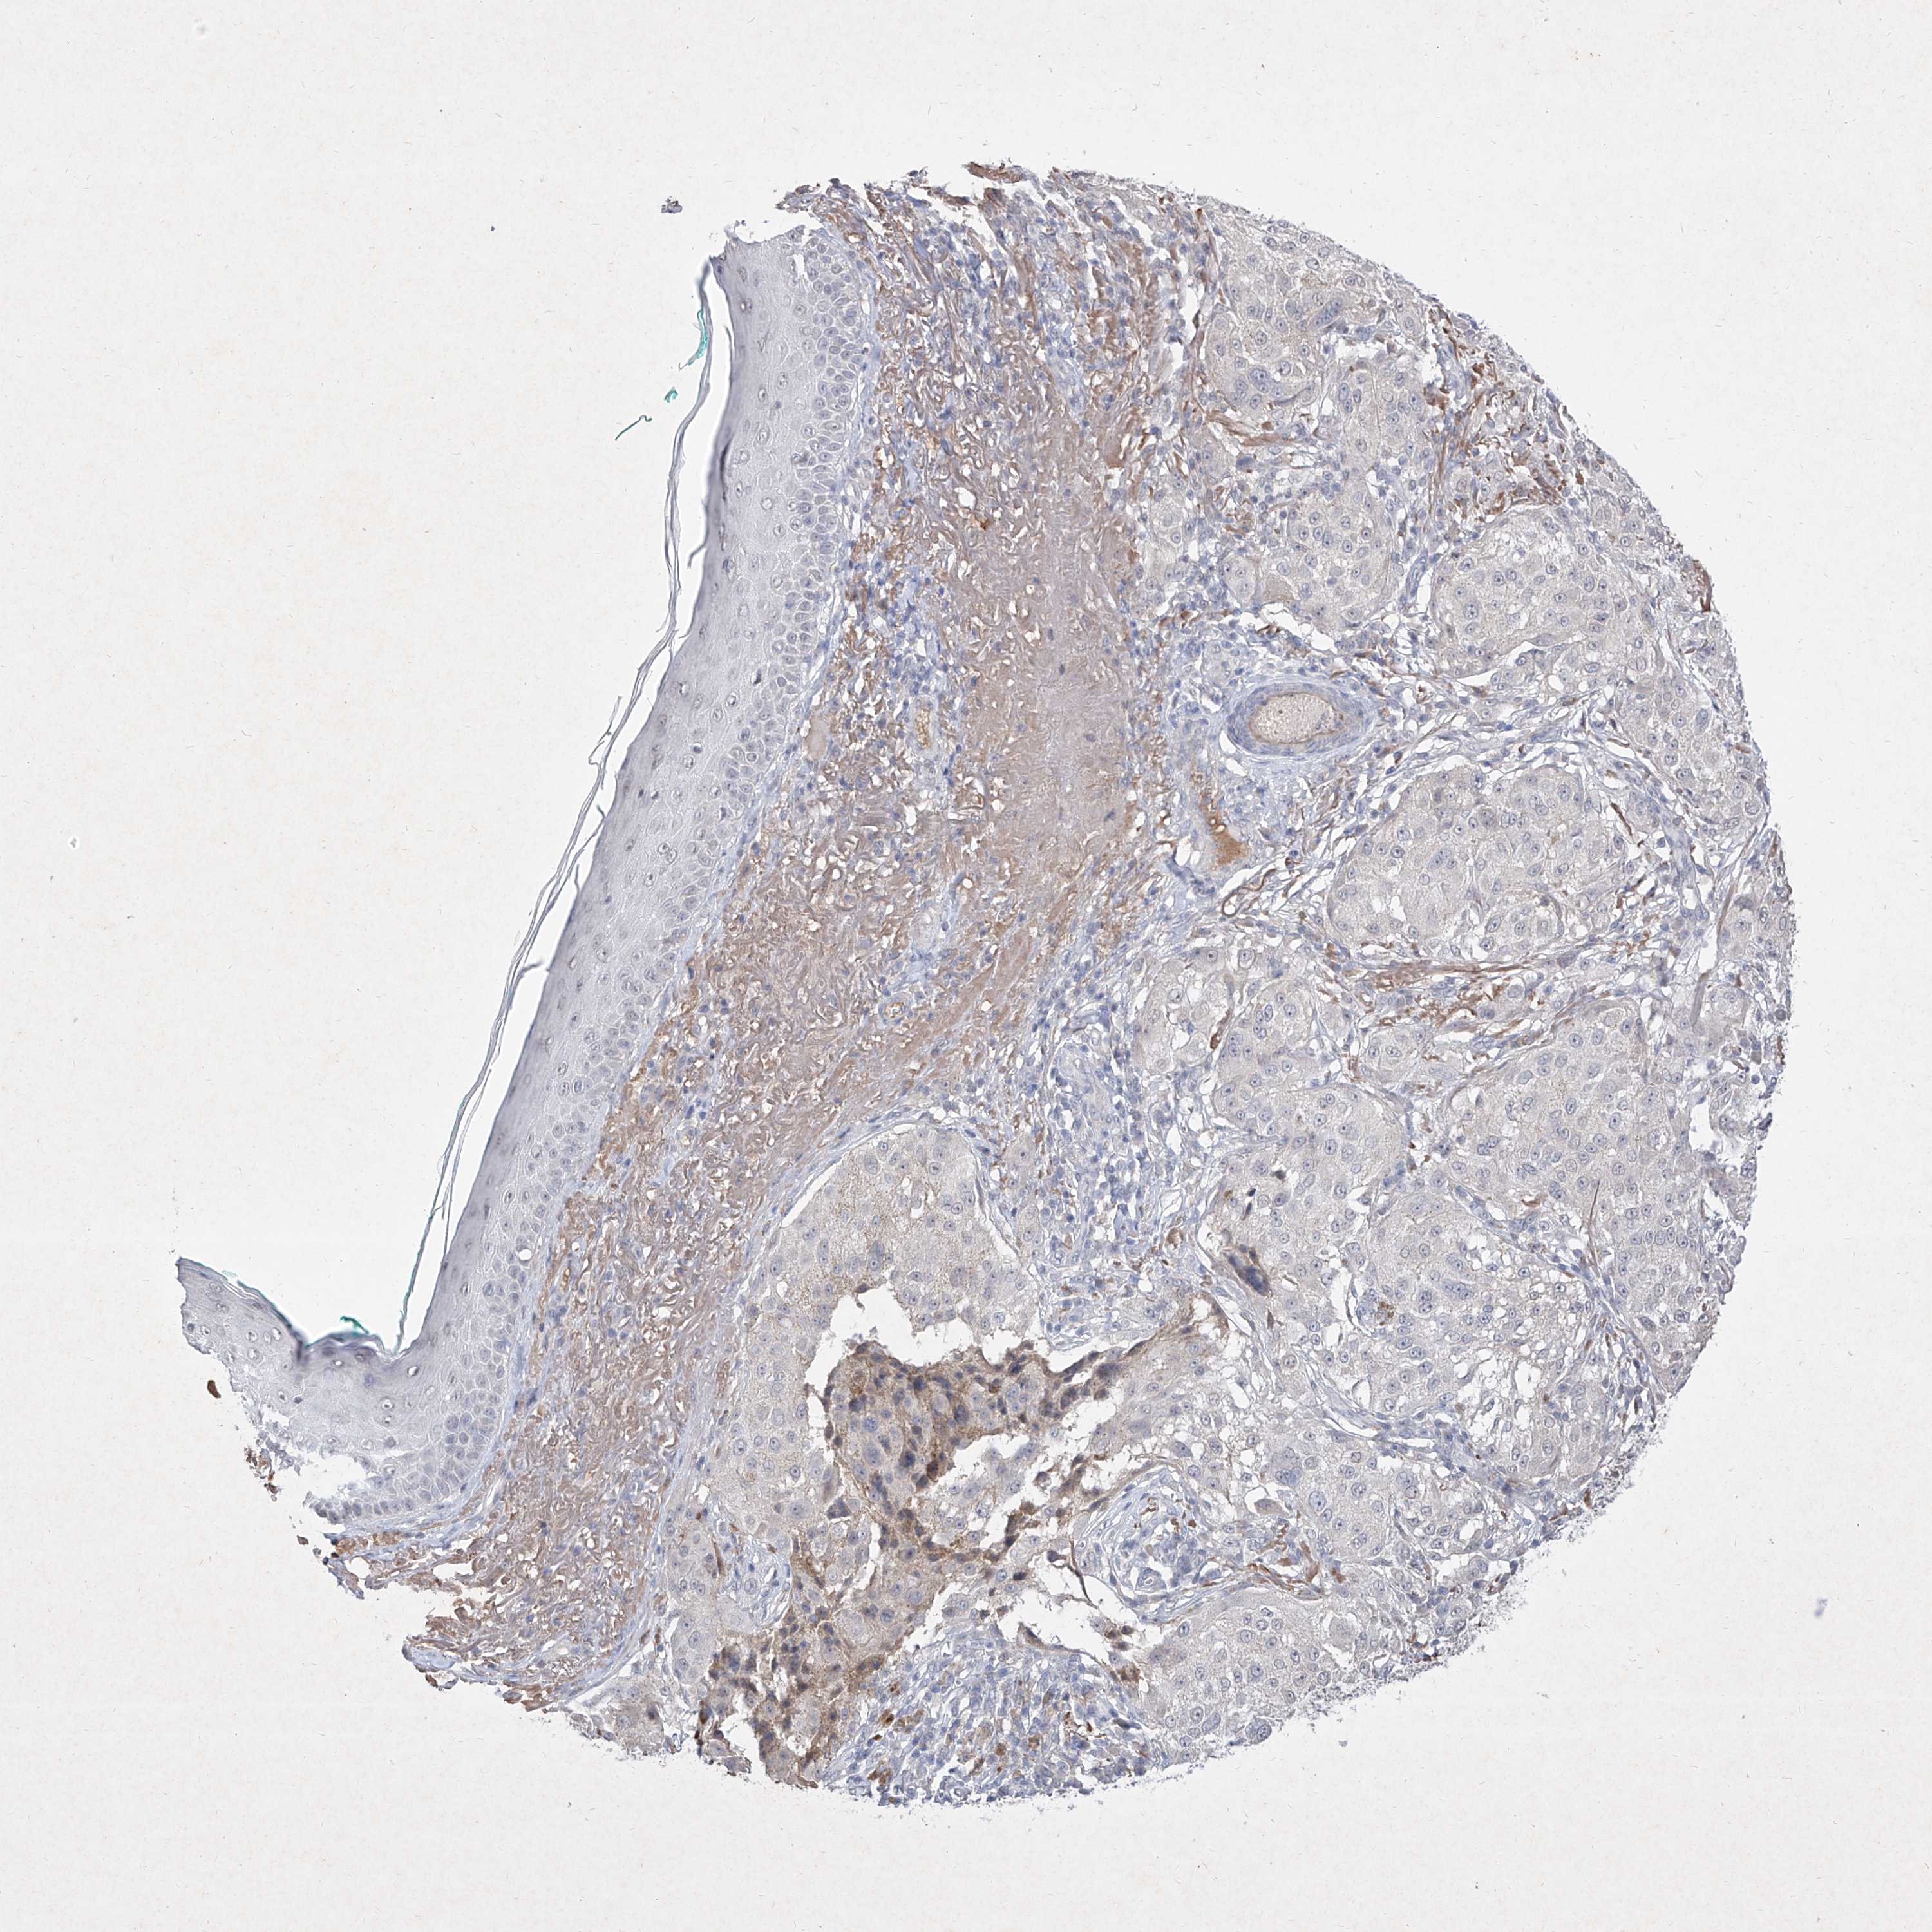

MELANOMA - Protein expressioni

A mouse-over function shows sample information and annotation data. Click on an image to view it in a full screen mode. Samples can be filtered based on level of antibody staining by selecting one or several of the following categories: high, medium, low and not detected. The assay and annotation is described here.

Note that samples used for immunohistochemistry by the Human Protein Atlas do not correspond to samples in the TCGA dataset.

Antibody stainingi

Antibody staining in the annotated cell types in the current human tissue is reported as not detected, low, medium, or high, based on conventional immunohistochemistry profiling in selected tissues. This score is based on the combination of the staining intensity and fraction of stained cells.

Each image is clickable and will lead to virtual microscopy that enables deeper exploration of all samples and also displays staining intensity scores, fraction scores and subcellular localization as well as patient and tissue information for each sample.

Malignant melanoma, NOS

Malignant melanoma, Metastatic site